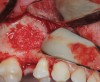

Fig 13. Lateral window closure with PRF membranes.

Figure 13